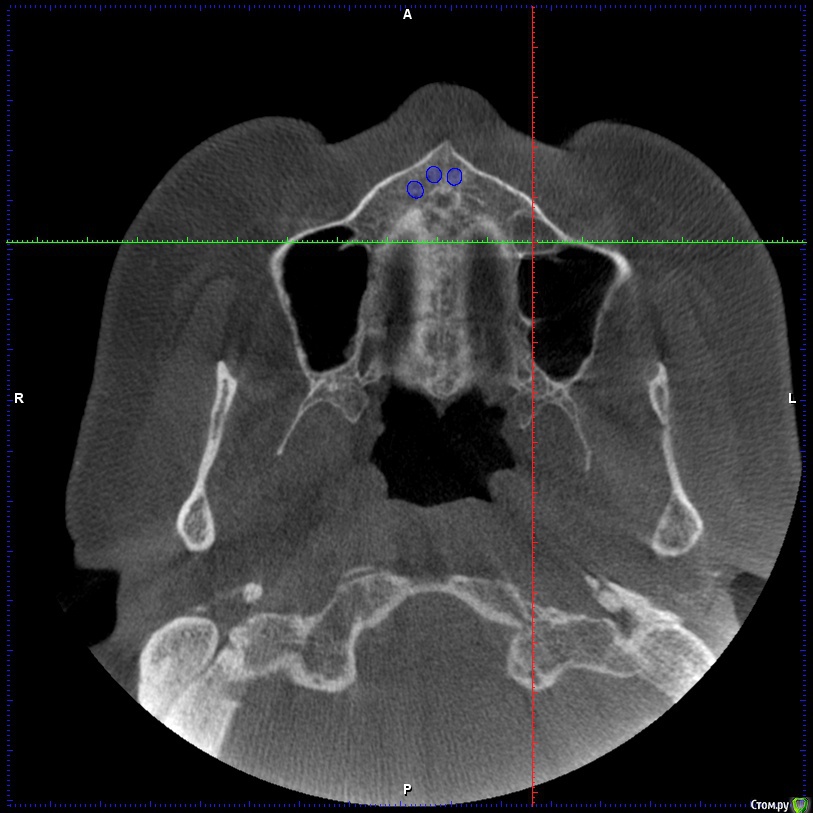

Aleksey_Mironov Опубликовано 11 января, 2018 Поделиться Опубликовано 11 января, 2018 здравствуйте коллеги!! вот такой сюрприз..хочу сделать синус лифтинг.. что за образование можеть быть? Ссылка на комментарий

Aleksey_Mironov Опубликовано 11 января, 2018 Автор Поделиться Опубликовано 11 января, 2018 здравствуйте коллеги!! вот такой сюрприз..хочу сделать синус лифтинг.. что за образование можеть быть? Ссылка на комментарий

Борис80 Опубликовано 11 января, 2018 Поделиться Опубликовано 11 января, 2018 Не совсем уверен, тк недостаточно срезов видно, но я бы сказал насморк или что-либо подобное(это по поводу тени) и , что значительно неприятнее, это костная перегородка на дне пазухи Ссылка на комментарий

колесников Опубликовано 11 января, 2018 Поделиться Опубликовано 11 января, 2018 (изменено) Может образоваться перфорация мембраны. Делайте 2 окна Изменено 11 января, 2018 пользователем колесников Ссылка на комментарий